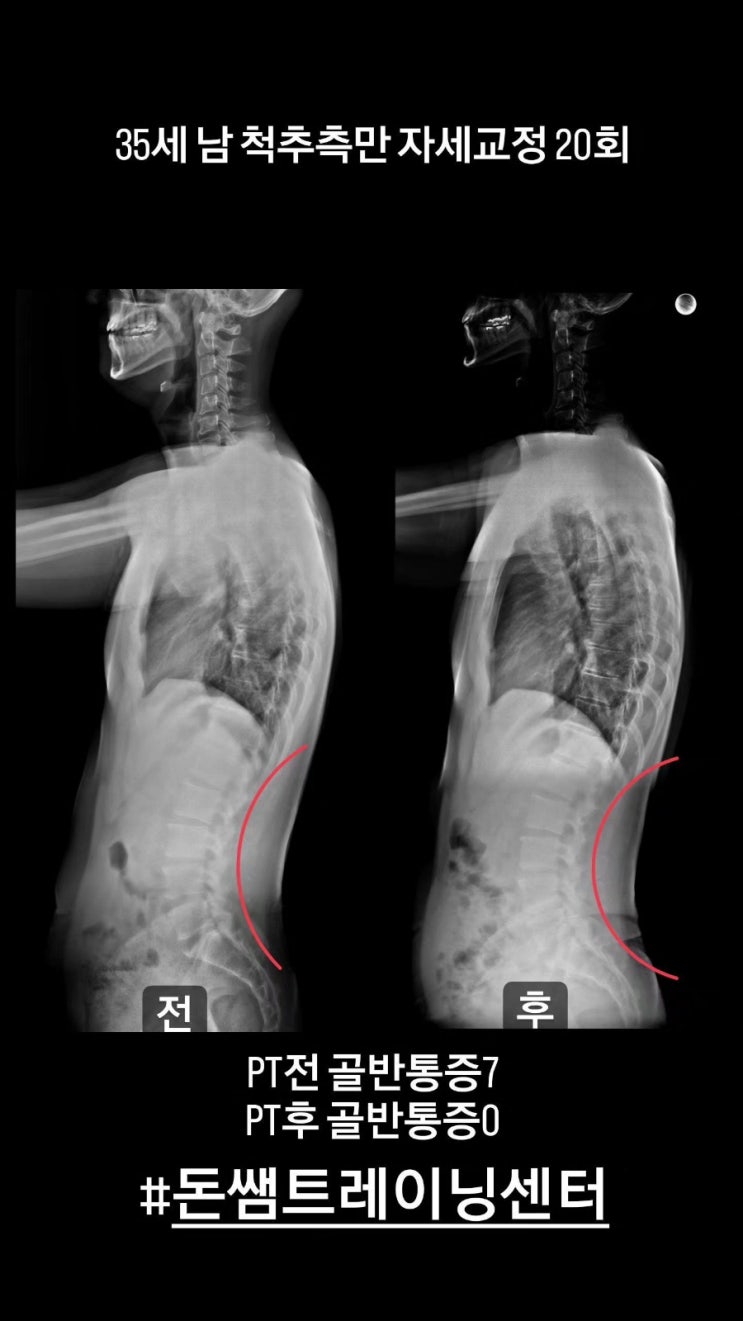

35세남 군포척추측만교정

군포척추측만교정 포스팅입니다 35세남성이고 직업 특성상 하루 종일 서서 일을 하셔서 짝다리 포지션을 많...